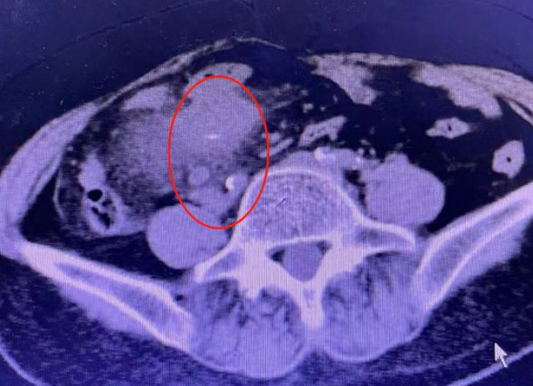

唐成祥醫(yī)生仔細(xì)地閱讀了王大姐之前的CT檢查,在她的右下腹發(fā)現(xiàn)條形的高密度影。這個(gè)高密度影引起了唐成祥醫(yī)生的警覺(jué),高密度影周?chē)哪c管還有輕微的增厚和滲出。經(jīng)過(guò)跟患者的溝通唐成祥醫(yī)生基本判定腹腔里的異物就是魚(yú)刺,且極有可能已經(jīng)扎穿腸壁。如果不抓緊處理,魚(yú)刺鉆出腸道刺破大血管,就要進(jìn)行外科切除小腸手術(shù),隨時(shí)會(huì)有生命危險(xiǎn)。

唐成祥醫(yī)生與患者家屬溝通之后,馬上為患者王大姐安排了小腸鏡手術(shù)。術(shù)中,經(jīng)肛小腸鏡的時(shí)候,發(fā)現(xiàn)回腸腺段有一個(gè)微小的破潰,魚(yú)刺已穿破小腸壁到達(dá)腹腔,形成了一個(gè)潰瘍。唐成祥醫(yī)生用鈦夾封住了創(chuàng)面。緊接著聯(lián)系了外科醫(yī)生做了個(gè)腹腔鏡,找到魚(yú)刺并取出。